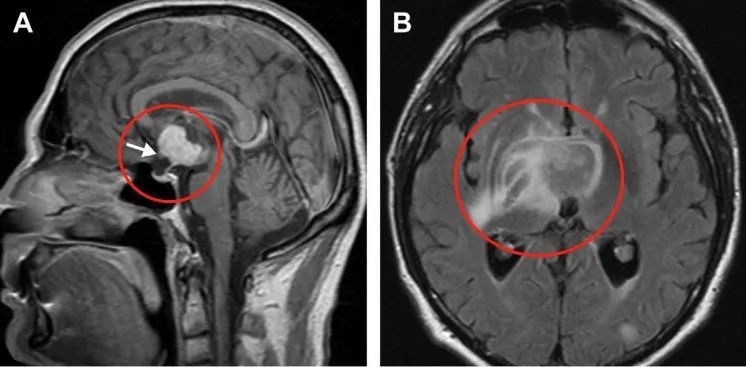

鞍上增强MRI显示,颅咽管瘤延伸至第三脑室,有实性成分(a)。视神经交叉前移(箭头标记),垂体和蝶鞍形态正常。病灶向右侧基底节区外侧延伸,且周围水肿,具有下丘脑侵犯征象。